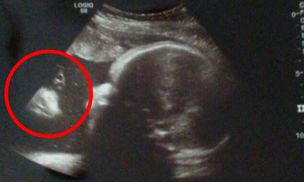

Para zobaczyła na USG dziecka… Jezusa